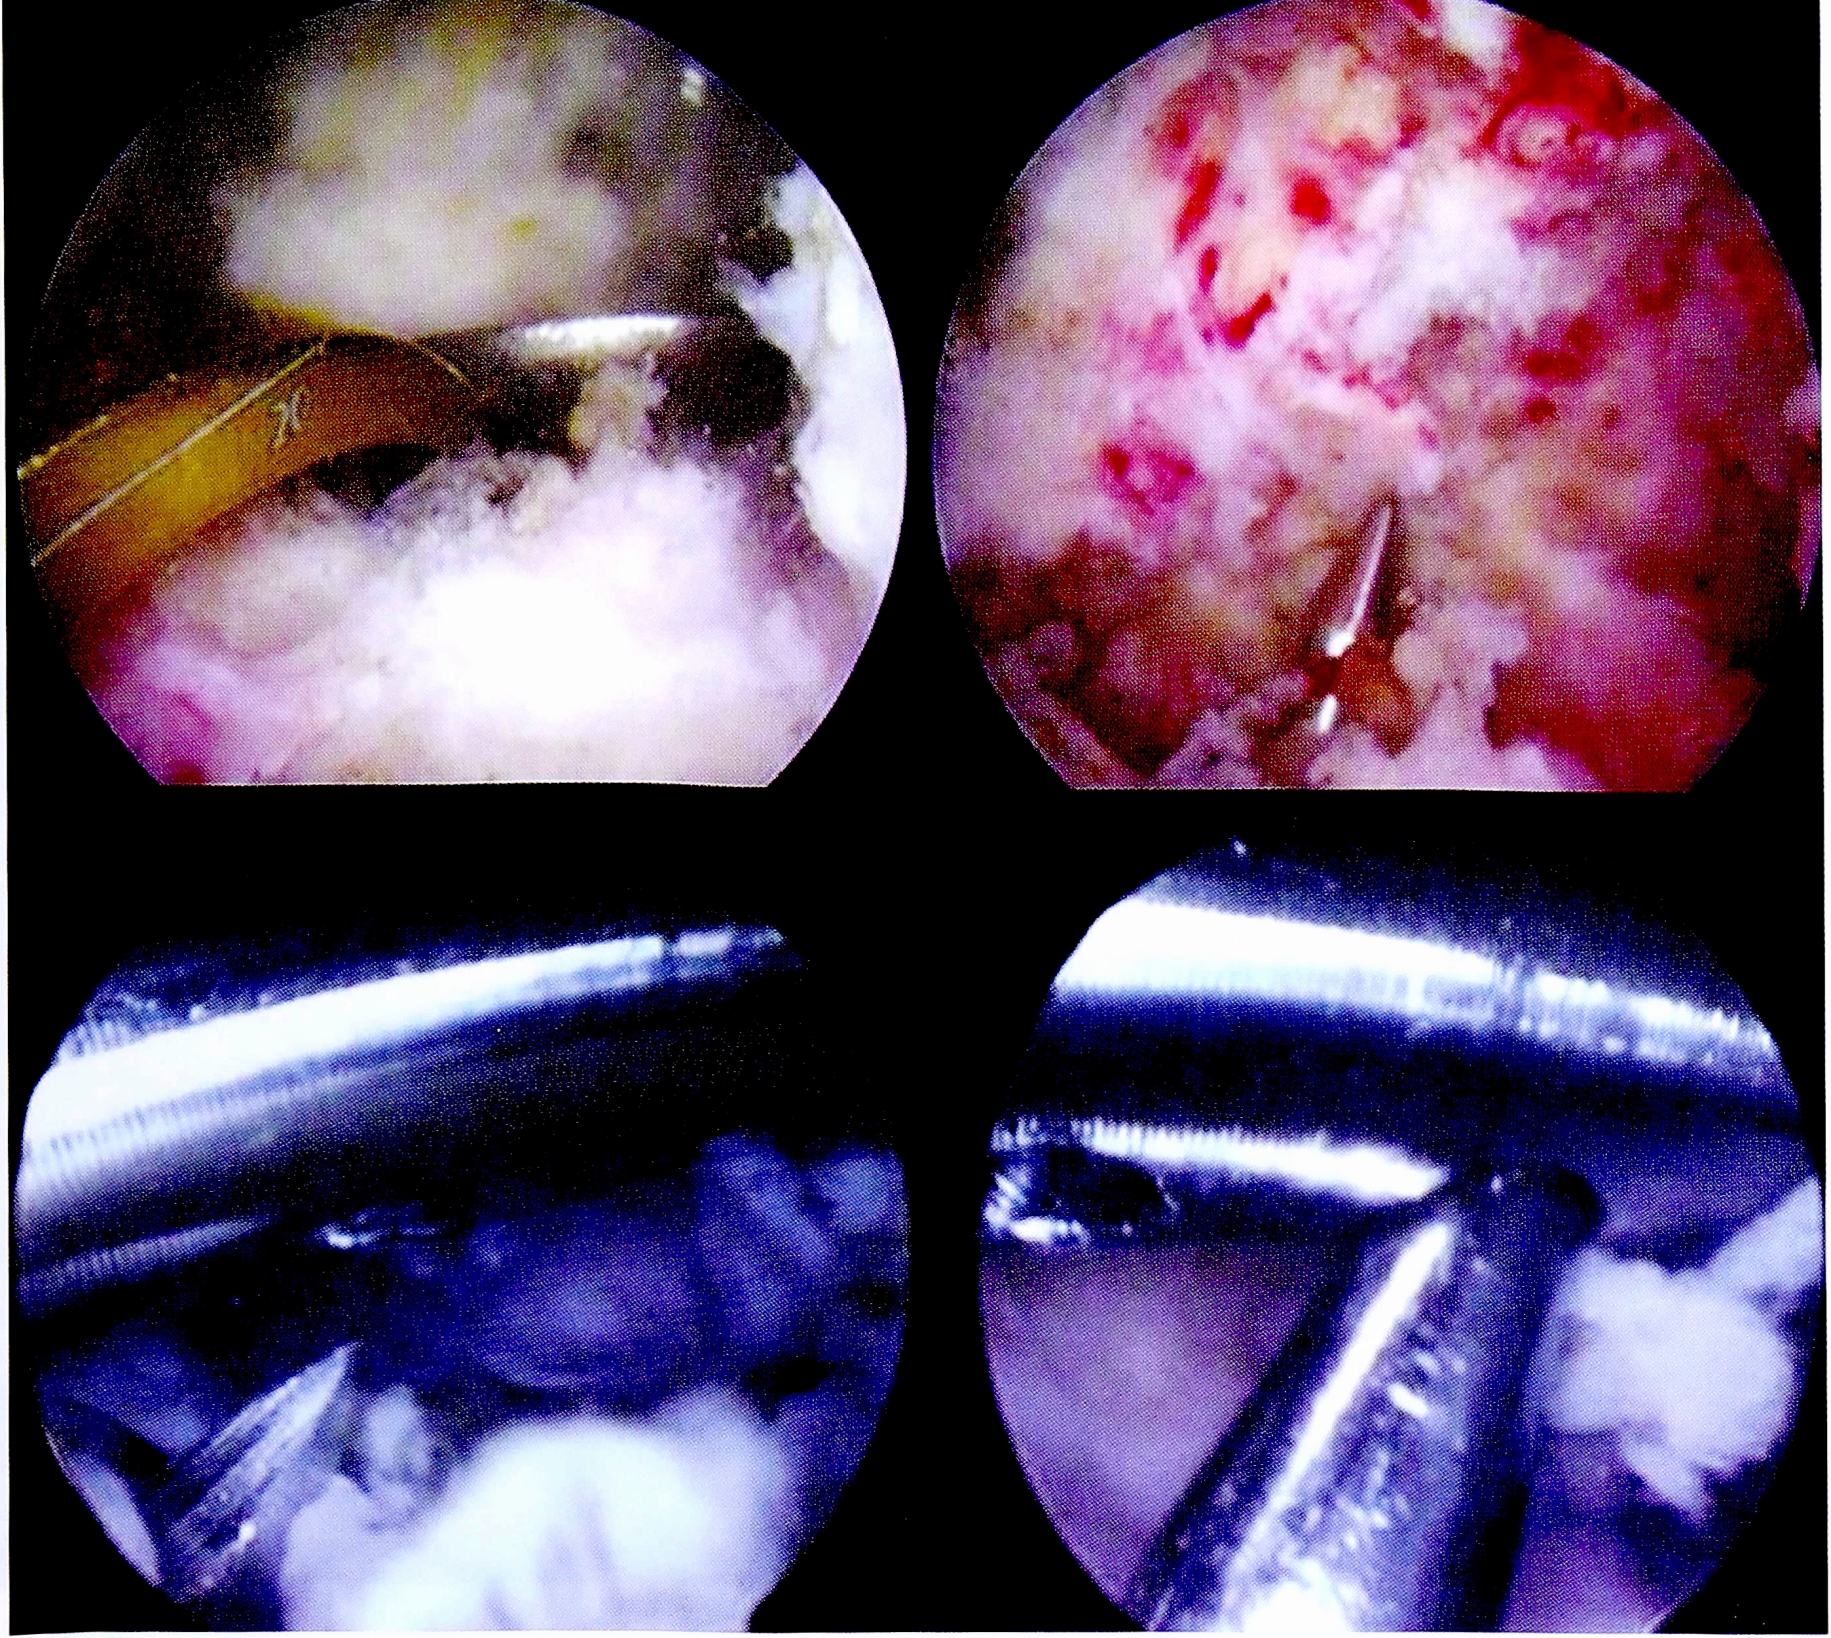

Следующим этапом осуществлялось иссечение рубцовой ткани и фрагментов поврежденных крестообразных связок в межмыщелковом пространстве. Особое внимание уделялось визуализации заднего отдела сустава и заднего межмыщелкового пространства вследствие обязательного формирования дополнительного заднемедиального порта (рис. 3).

Рис. 3. Дебридмент, резекция культи ЗКС.

Fig. 3. Resection of PCL fibers, debridment.

Формирование костных тоннелей проводилось с использованием направителей из набора для пластики крестообразных связок. Костный тибиальный тоннель для ЗКС создавался согласно разработанной методике, через латеральный мыщелок, с выходом в зоне задней межмыщелковой ямки на 15 мм ниже щели сустава (рис. 4).

Рис. 4. Артроскопическая картина формирования тибиального костного тоннеля для пластики ЗКС.

Fig. 4. Making of tibial bone tunnel.

Бедренный костный тоннель формировали согласно анатомическому положению нативной ЗКС — в положении «1,5—2 ч» (для правого коленного сустава), на 3-4 мм кзади от заднего края хряща мыщелка бедренной кости (рис. 5).

Рис. 5. Артроскопическая картина формирования феморального костного тоннеля для пластики ЗКС.

Fig. 5. Making of femoral bone tunnel.

Предварительно измеренные и подготовленные сдвоенные аллогенные сухожилия последовательно проводились в костные тоннели (рис. 6).

Рис. 6. Протягивание и установка аллотрансплантата ЗКС через костные тоннели.

Fig. 6. Positioning of the PCL allograft through the bone tunnels.

После проведения и фиксации на бедренной кости трансплантата ЗКС формировались костные тоннели для пластики ПКС. Использовались стандартная транстибиальная методика и набор направителей для ее выполнения (рис. 7).

Рис. 7. Артроскопическая картина основных этапов пластики ПКС.

Fig. 7. Main stages of ACL plasty.